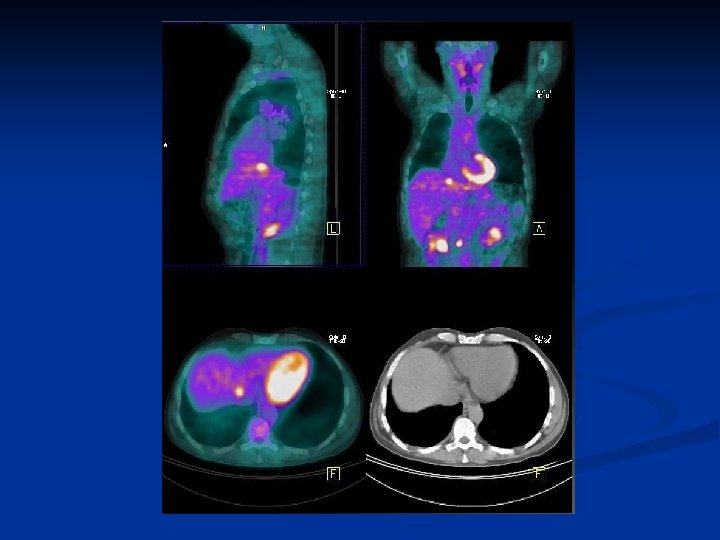

CAS CLINIQUES

Cancer pulmonaire n n n Homme 48 ans Carcinome épidermoide LSD traité par radiothérapie + chirurgie Image douteuse au niveau hépatique et rénale